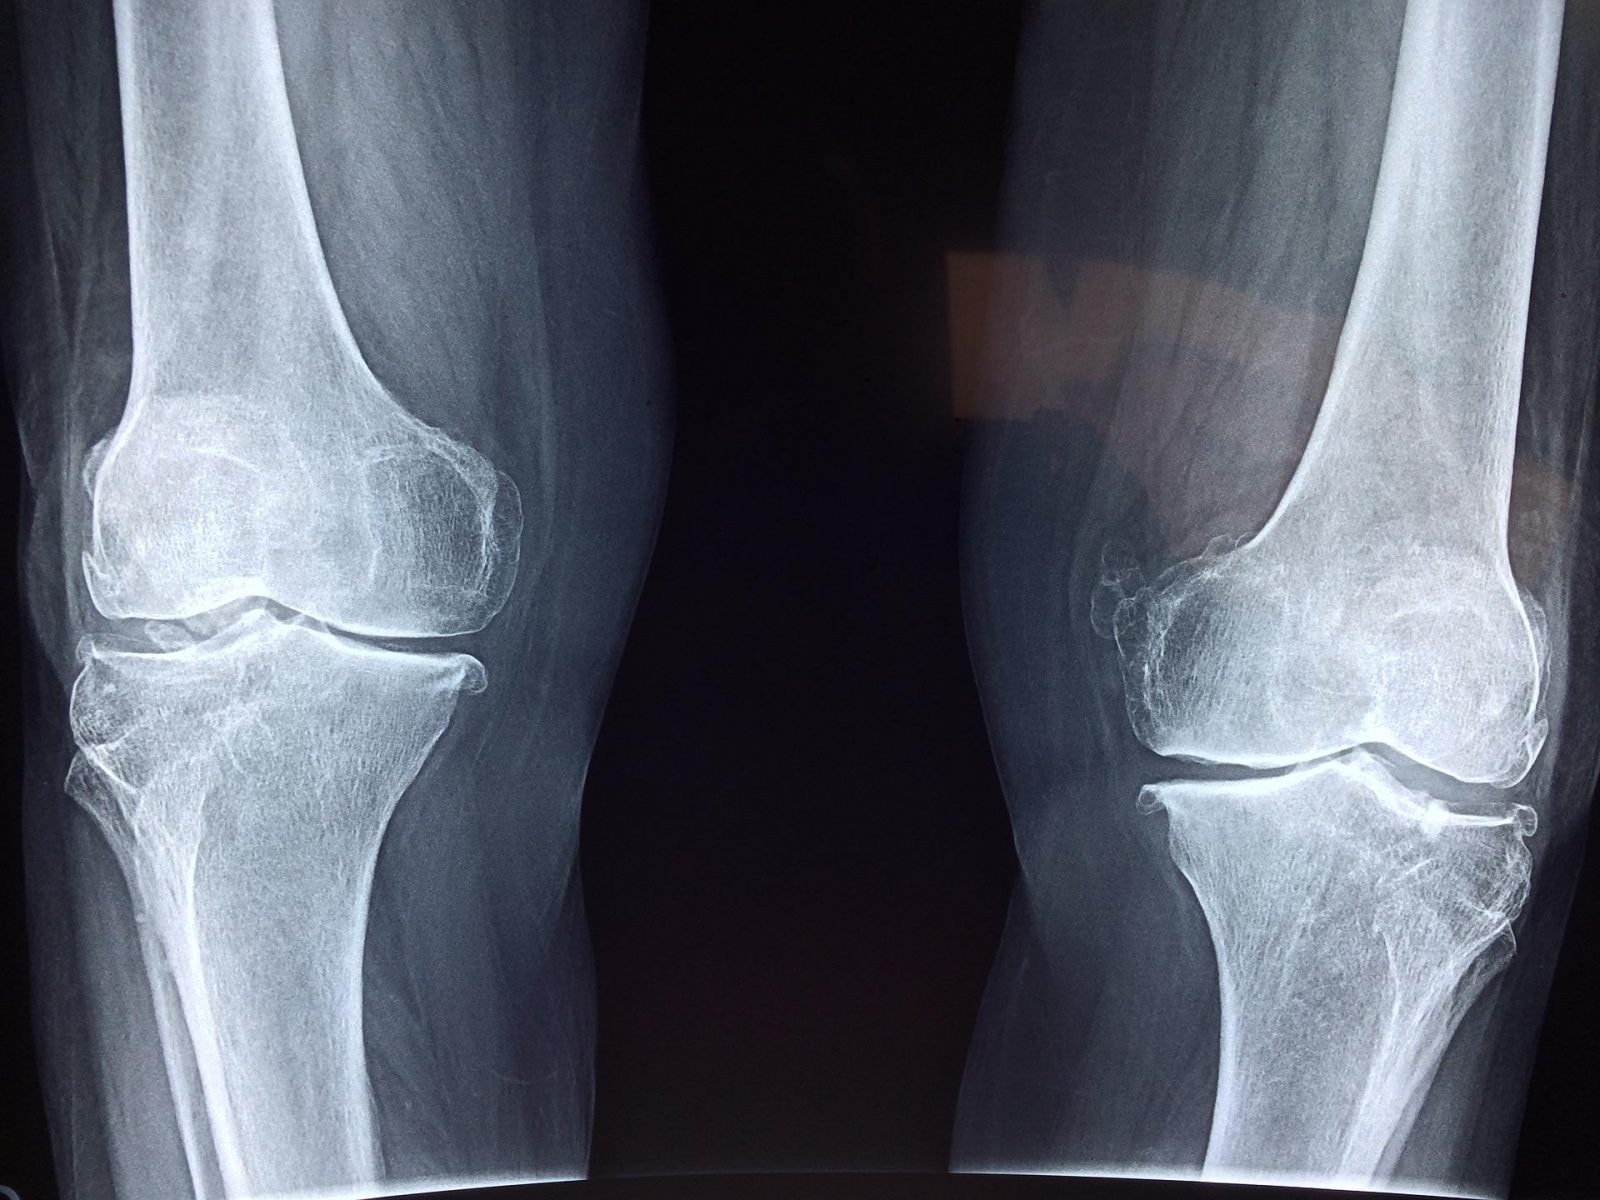

Ból kolana często jest wynikiem postępującego choroby zwyrodnieniowej stawów, na którą cierpi 867 mln ludzi na świecie. Jest to konsekwencja postępującego zużycia chrząstki stawowej, którą zazwyczaj trzeba wymienić. Wkrótce może pojawić się alternatywna forma leczenia pozwalająca błyskawicznie stanąć pacjentom na nogi – i zapomnieć o bólu.

Wstępne testy substytutu chrząstki opracowanego na Duke University wykazały, że materiał wykonany z polimerów pochłaniających wodę może być ściskany i ciągnięty z większą siłą niż naturalna chrząstka. Jest przy tym trzy razy bardziej odporny na zużycie.

W testach zużycia, badacze porównali sztuczną i naturalną chrząstkę, które obracali je względem siebie milion razy, z naciskiem podobnym do tego, jakiego kolano doświadcza podczas chodzenia. Wykorzystując tomografię mikrokomputerową (micro-CT), potwierdzono, że syntetyczna chrząstka była trzy razy bardziej odporna od naturalnej. Ponieważ hydrożel naśladuje gładką, śliską i miękką naturę prawdziwej chrząstki, chroni on inne powierzchnie stawowe przed tarciem, gdy ślizgają się one o implant.